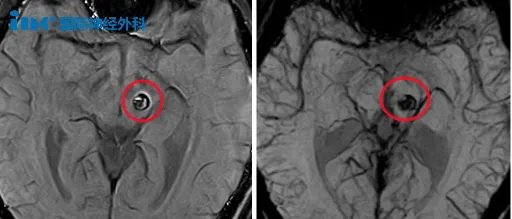

▼2023年6月23日,小林第1次出血

小林母亲每每回想起孩子第一次出血的情景,医生的话就像一声晴天霹雳,顿时让他们心情沉重、如坠深渊。“当时孩子有点头疼头晕,脸有点麻,核磁查出来了。医生就说可能是一个海绵状血管瘤。后来我们又到了北京,医生看了一下,说这个没法动手术的。只要动是90%以上会瘫痪。别说90%,50%我也不敢让他动,因为孩子才18岁。没办法,回来之后就是保守治疗。”

但这一次出血,症状较轻,表现为右侧手臂和腿部麻木,面部麻木,可以正常行走。小林休息几天之后症状减轻,着急上学的他尽早就回到了校园。

▼2024年1月7日,小林第2次出血

第2次出血更是让小林母亲后怕不已:“保守观察到2024年1月份,头疼头晕再次出血,因为那段时间他总是熬夜凌晨。医生说治不了,在ICU待了几天也没有动手术。”